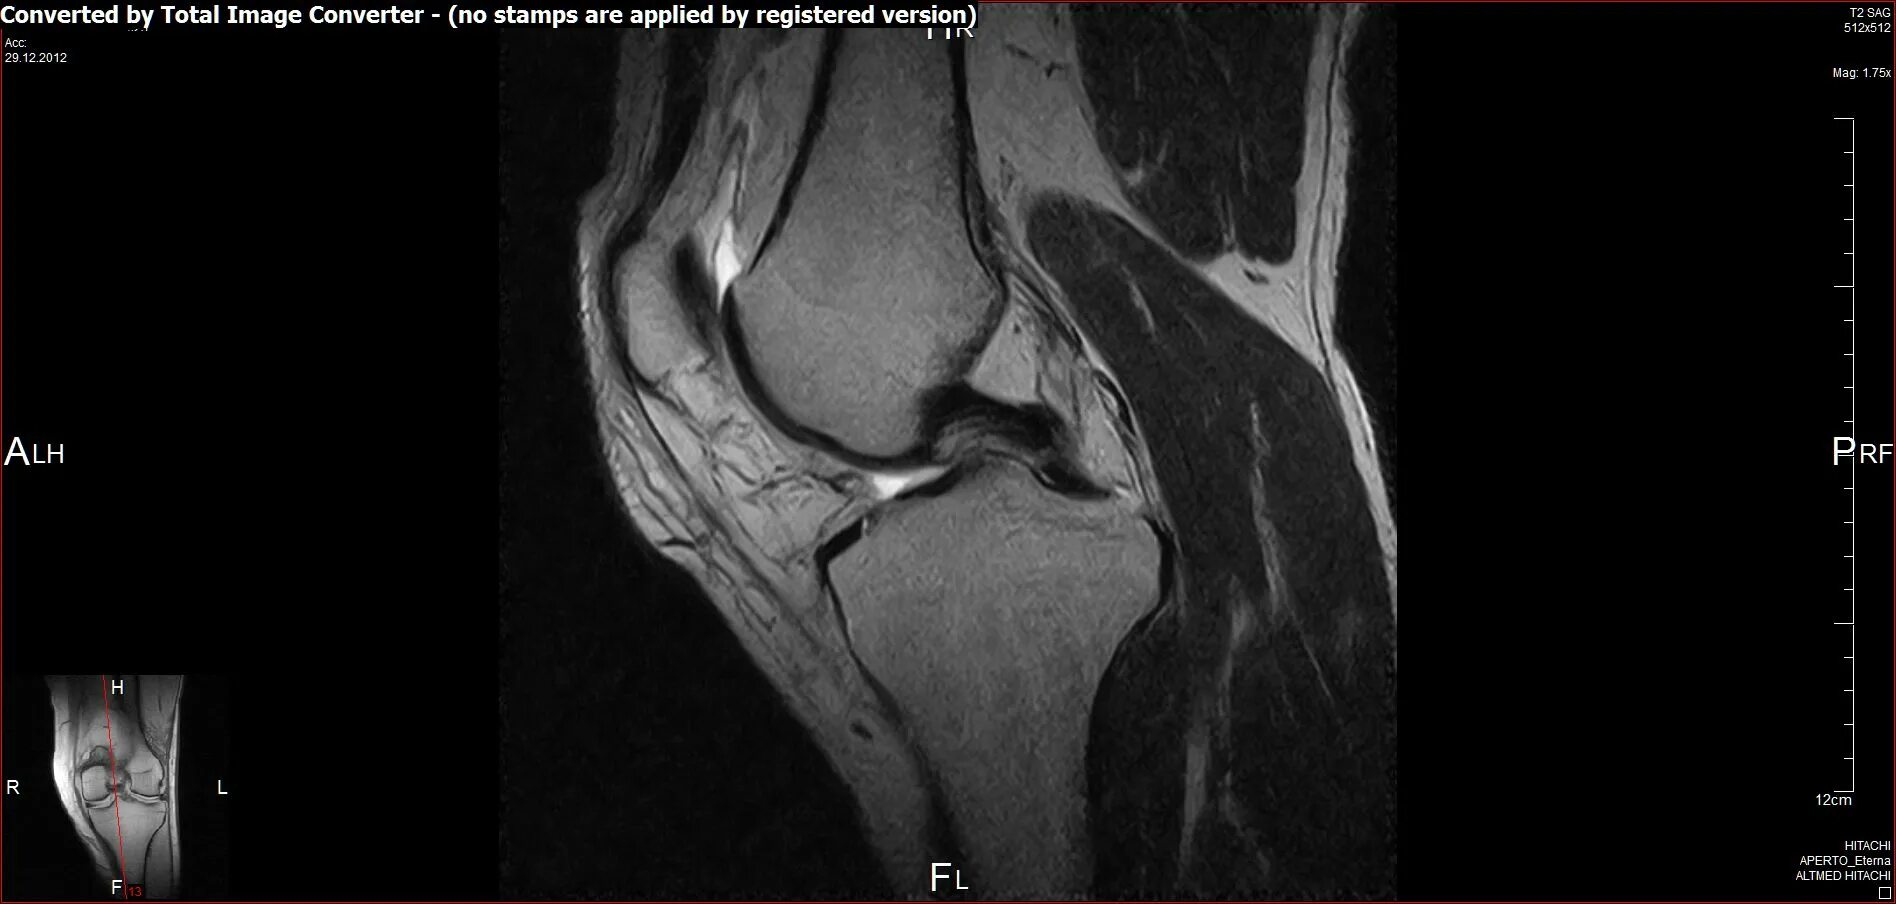

Мрт коленного сустава одежда